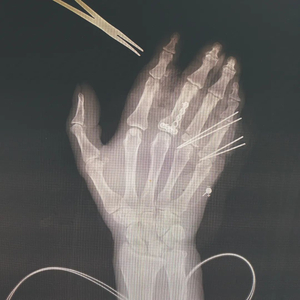

李芸右手断指再植入后图像。供图/无锡市第九人民医院

62岁的李芸右手三指截断,手术前影像(手背朝上)。供图/无锡市第九人民医院

在给李芸做的手术中,钱俊先要给其清创,将铁屑等创面上的异物去除,避免造成感染,然后用克氏针(一种钢针)将李芸截断的骨骼和断指处还保有的骨骼串起来,固定回原位,这好比房子重建时要用钢筋先搭起框架。

在骨骼固定后,他将李芸被利器斩断缩回手掌的肌腱找出,再需缝合每根断指承担手指伸屈功能的两根肌腱、两根动脉、两根静脉及两根神经。血管吻合是关键。手指血管形态宛如树木伸出枝桠,指根部血管较粗,直径为1毫米,指尖部位只有0.3毫米左右。缝血管的线至少在微米级别,比头发丝还细,放在桌上根本难以看出。缝合好后,一般要观察7-10天,保证血运通畅,避免血管痉挛或者血管里形成血栓。